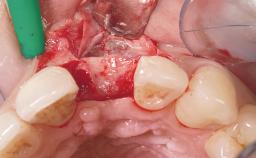

Immediate Flapless Placement of an Implant in a Maxillary Left Central Incisor Site

A 29-year-old female patient presented for treatment to replace the upper left central incisor tooth with an implant- supported restoration. The tooth had been intermittently symptomatic for the previous 12 months. The tooth had originally suffered trauma about 15 years previously. Several endodontic treatments had been performed, including an apicectomy procedure to retain the tooth. The patient was healthy and a non-smoker. She had reasonable expectations in regard to esthetic outcomes and the risk of marginal tissue recession following treatment. At medium smile, the gingival margins of the upper teeth were visible, with a display of 3 to 4 mm of the gingival margins. Gingival recession of tooth 21 and a discrepancy in the gingival levels between teeth 11 and 21 was observable during normal speech and smile.

Area Anterior

Socket Integrity Damage to one or more bone walls

Bone Volume Damage to one or more socket walls

Complexity Moderate

Risk of Complications High